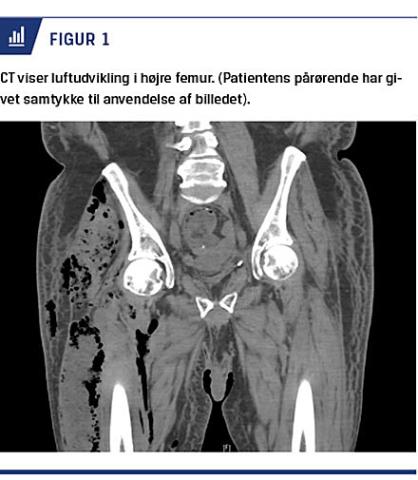

På ortopædkirurgisk anbefaling udførtes en akut CT af højre femur, hvorved man fandt en præsakral absces med fri intraabdominal luft og massiv luftudvikling i højre UE (Figur 1). På mistanke om gasgangræn blev patienten akut opereret, og en absces med massivt fækulent indhold samt nekrose af subcutis, fascier og muskulatur i højre UE lokaliseredes.